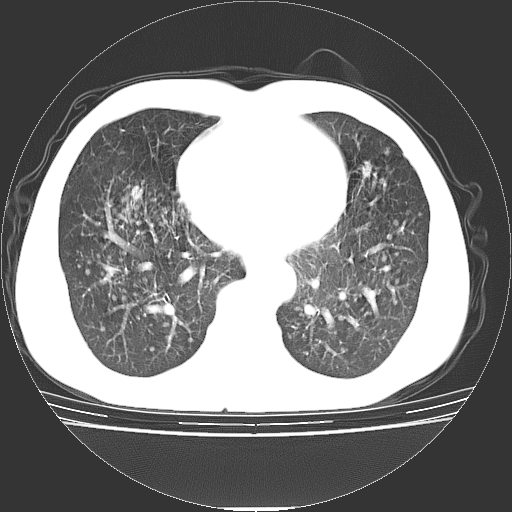

以下是引用yangyudong333在2008-4-29 5:38:00的发言:[br]比较典型的矽肺结节.支持[br]诊断依据:[br] 1.x线表现:[br] ①典型矽肺为多发直径 1~3mm 小结节,即矽结节,由胶原纤维和硅尘构成,可融合成团块,好发于上肺。[br] ②团块周围常有肺大泡。[br] ③胸内淋巴结增大、钙化。如肺门淋巴结呈蛋壳样钙化有助于与其他尘肺区别。[br] ④胸膜常广泛粘连、增厚。[br] 2.ct表现[br] ①两肺散在大小较为一致的小结节影,其密度较高,边界清楚。[br] ②小结节可融合为较大团块影,直径约 1cm ,甚至可达 10cm以上,易发生在上叶。[br] ③小结节周围常并有小叶中心气肿或弥漫性肺气肿。

以下是引用liuyue在2008-4-28 22:30:00的发言:[br]比较典型的矽肺结节.[br]请结合临床及化验除外矽肺合并肺结核之可能.